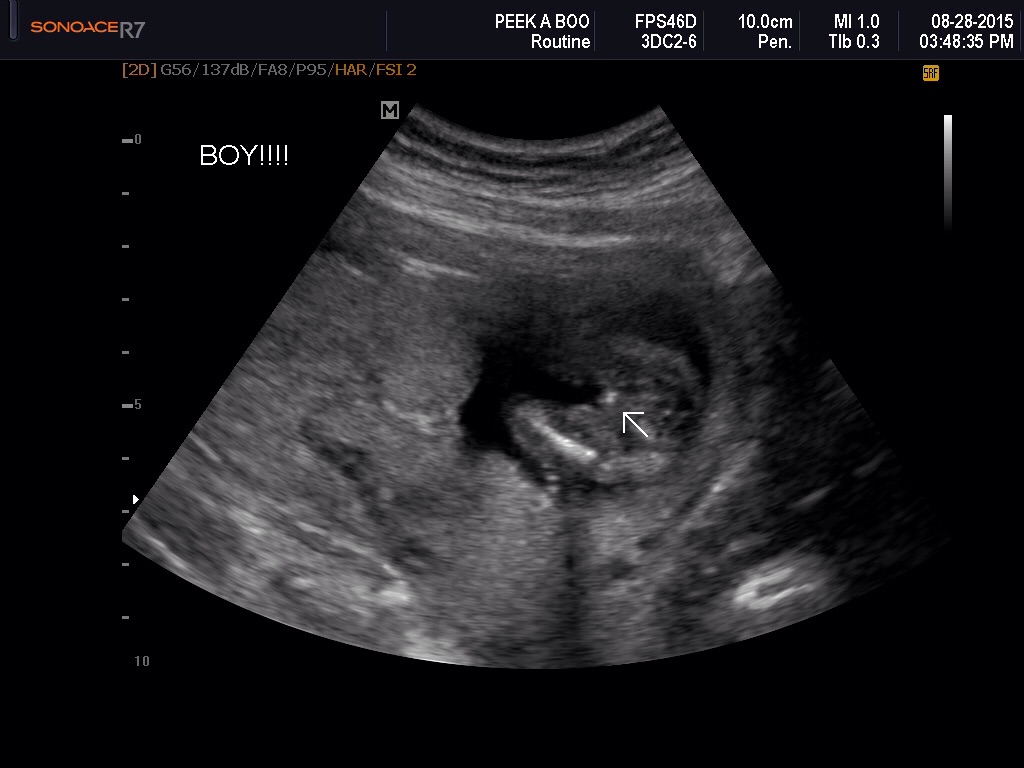

Ultrasound tech was sure a boy, but I don't know!!! What do you think??Attachment 28099